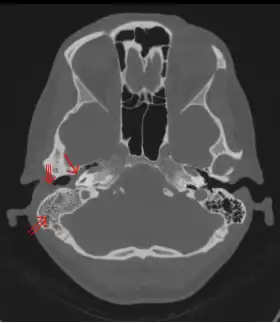

Diagnosis

The diagnosis of mastoiditis is clinical—based on the medical history and physical examination. Imaging studies provide additional information; The standard method of diagnosis is via MRI scan although a CT scan is a common alternative as it gives a clearer and more useful image to see how close the damage may have gotten to the brain and facial nerves. Planar (2-D) X-rays are not as useful. If there is drainage, it is often sent for culture, although this will often be negative if the patient has begun taking antibiotics. Exploratory surgery is often used as a last resort method of diagnosis to see the mastoid and surrounding areas.[2][9]